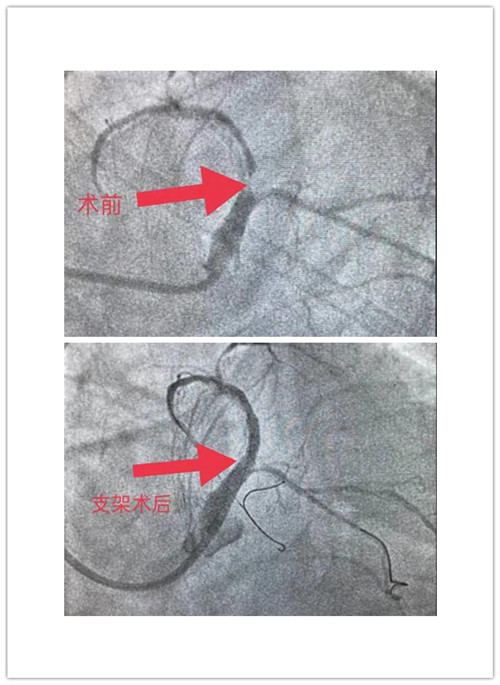

重症医学科主任王秋艳、医生于红波及其介入团队成员整装待备,为抢救患者生命争分夺秒。上肢入路迂曲,果断改为下肢通路,造影显示左主干严重狭窄,只剩下一条缝隙,右冠95%狭窄,选用EBU3.5指引导管,导丝过去以后血流中断,血压下降,血氧饱和度低至80%,呼吸困难症状加重,口唇紫绀,立即给予无创呼吸机辅助呼吸,多巴胺等药物升压,预扩2.5*15mm球囊预扩张,为生命的延续划出最后一道余光。在生死面前,人人平等,每个人都享有生命的权利。此时患者的生命体征显示死神真的来了,但重症医学科介入团队镇定自如,技术娴熟,稳稳的把生命线握住。患者左主干病变严重钙化,王主任再次启用2.5*15后扩球囊继续扩张,为支架的充分膨胀做好准备,抽吸导管、Guidezilla支架延长导管、无创呼吸机等十八般武艺全盘托出。最后决定,立即放置左主干支架扩张血管。重症医学科介入团队一周内第三次上演与死神搏斗的精彩场景,顺利完成左主干支架植入术,保存了患者生命。参与抢救的重症医学科介入团队终于放松了紧张的情绪,露出了疲惫的笑容,此时大家的手术衣早已湿透了全身。

手术前后对比

目前,患者病情尚平稳,已脱离无创呼吸机,胸痛气短症状明显缓解,血压平稳,呼吸正常,心率在85-105次/分,AVR导联ST段回落到正常,在重症医学科进一步治疗中。患者及家属对重症医学科团队熟练的技术,救死扶伤、勇于担当精神表示感谢。